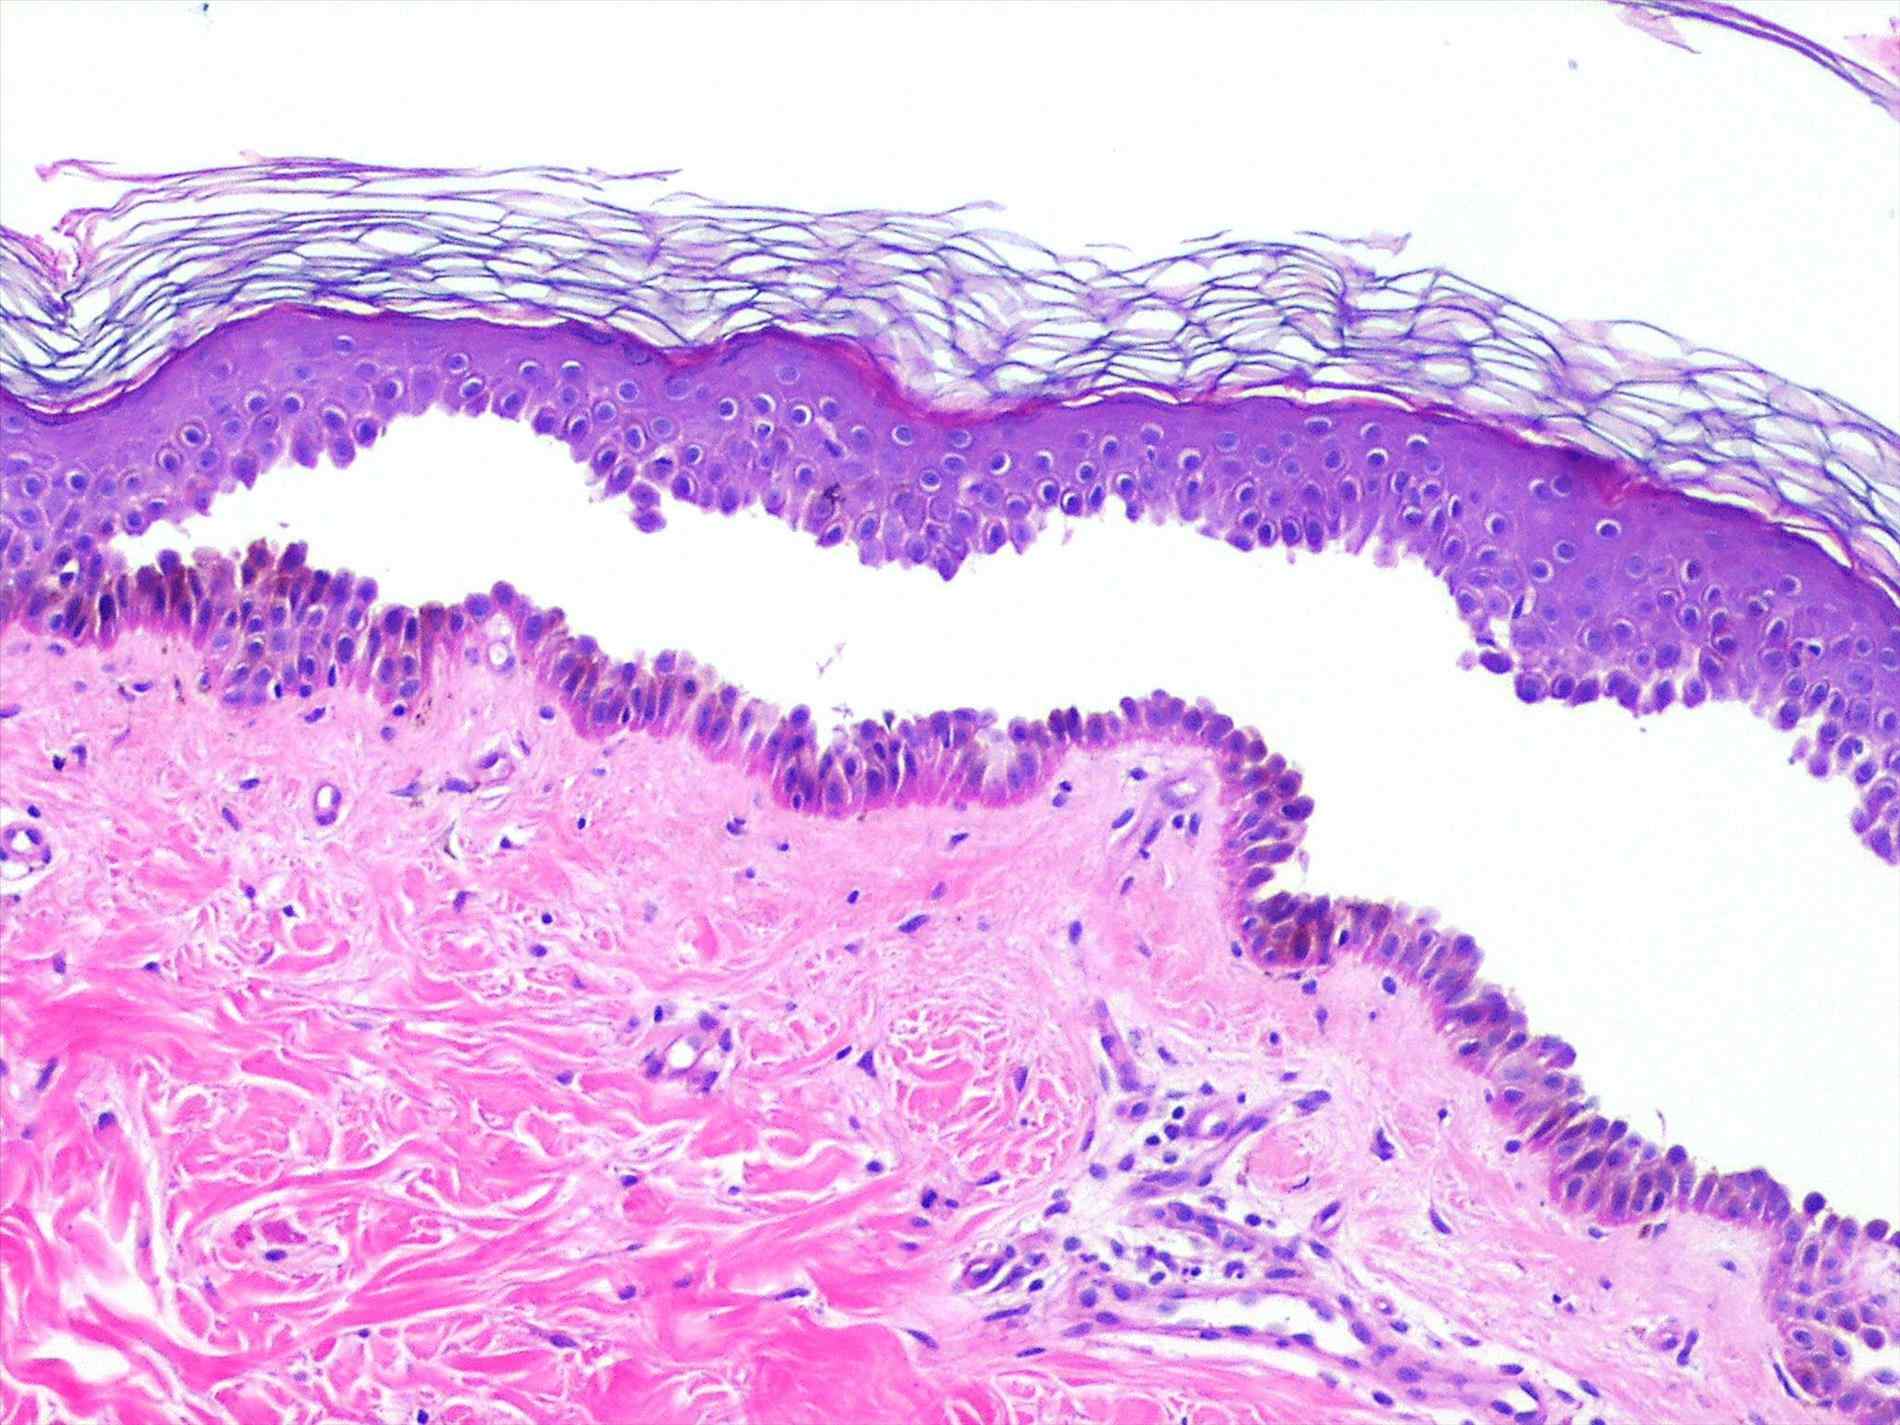

На образование кожи, способной противостоять внешней среде, уходит долгих девять месяцев жизни ребёнка в материнской утробе. Прямым родственником кожи является головной и спинной мозг. Кожный покров плотный, состоит из трёх частей. Самым верхним является эпидермис, который находится в непосредственном контакте с дружественными и болезнетворными микробами и другими внешними факторами. Работу по амортизации механических воздействий выполняет средний слой кожи — дерма. Её внутреннее строение во многом схоже с переплетёнными прутьями корзин или мебели. Запасает тепло нижний слой кожи — гиподерма, состоящая из скопления жировой ткани.

Кожа человека состоит из трёх слоёв

Особенностью кожи, в том числе детской, является её способность к ороговению. В эпидермисе ежедневно образуются роговые чешуйки, которые затем покидают его поверхность. На место отживших свой срок чешуек приходят новые, благодаря чему кожа постоянно обновляется. Между слоями кожи находятся нервные окончания, благодаря которым ребёнок с рождения способен осязать окружающий мир.

Эпидермис образован несколькими слоями клеток

В настоящее время основной причиной акантолитической пузырчатки считается агрессия собственной иммунной системы. В обычных условиях иммунные клетки патрулируют территорию организма и никогда не трогают родные ткани и органы. Причину, по которой эпидермис воспринимается иммунитетом как чужеродный объект, ещё предстоит установить учёным. Однако механизм развития пузырей на коже в настоящее время известен. Иммунные клетки лимфоциты образуют специфические средства борьбы с эпидермисом — антитела. Их воздействие на кожный покров приводит к разобщению слоёв эпидермиса — акантолизу. Между ними мгновенно оказывается тканевая жидкость и формируются пузыри. Заразиться такой формой пузырчатки от другого человека нельзя.

Акантолиз — причина образования пузырей при истинной пузырчатке

В диагностике пузырчатки используются следующие методы:

- изучение участка кожи под микроскопом позволяет выявить акантолиз.